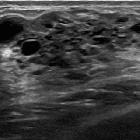

Breast ultrasound

They can appear as an ill-defined, inhomogeneous hypoechoic mass with multiple small (up to 4 mm) predominantly peripheral cysts. Microcalcifications may be seen at sonography .